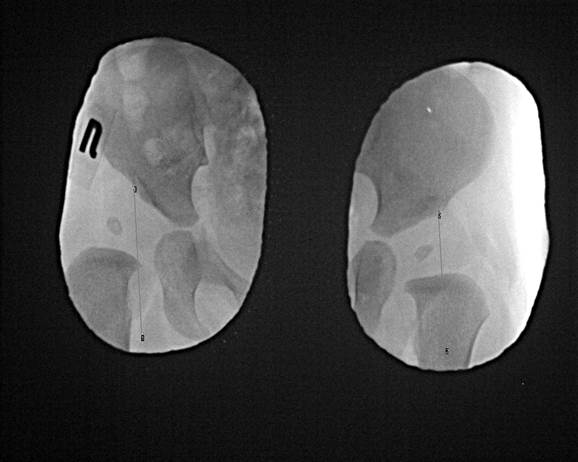

Ниже, Вашему вниманию, примеры исследований тазобедренных суставов младенцев грудного возраста.

Исследования проводились на цифровом рентгеновском аппарате, позволяющем производить необходимые измерения (показаны на снимках), для постановки точного диагноза и выбора правильной тактики лечения.

Негативное изображение